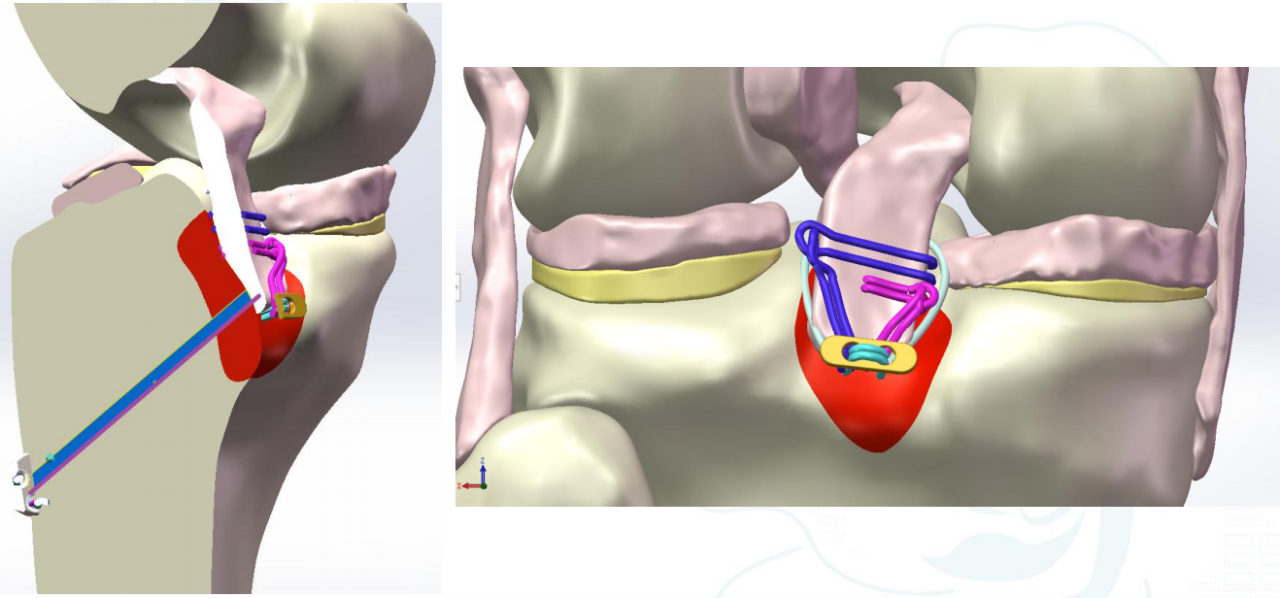

3D Model Demonstration

Ⅲ型:撕脱骨折块;BC>15mm;AE/AD≥1/2。

术式:双袢+后叉前建立骨道

步骤: 明确骨折、建立骨道、置袢复位骨折

ⅢA型:多块撕脱骨折块,BC>15mm,AE/AD>1/2;

术式:双袢(后叉前建立骨道)+高强线

步骤: 明确骨折、建立骨道、引入袢+预置高强线

步骤: 建立平台骨道、复位收袢